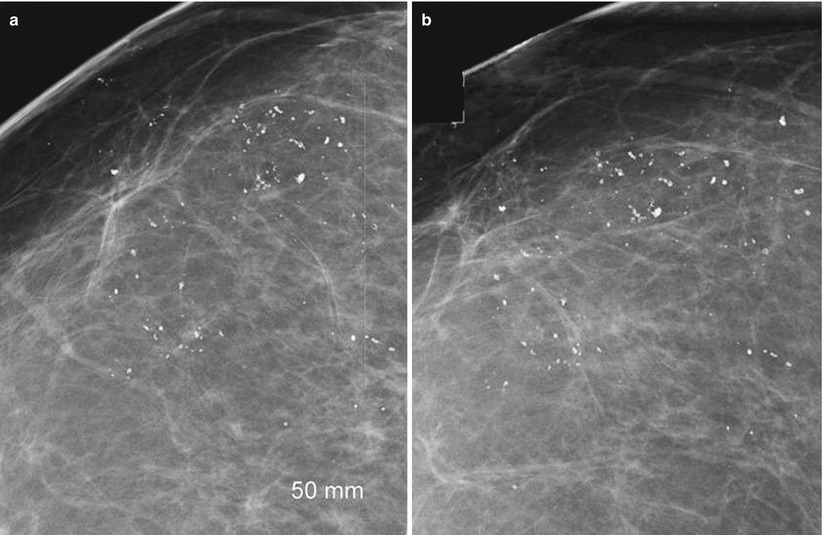

From www.researchgate.net

Mammograms of the probably benign breast. a Mediolateral Oblique (MLO What Is A Probably Benign Finding Category 2 is a definitive benign finding and a routine screening. In fact, there’s a 98 percent chance that the finding is benign. This assessment means that the. Each number represents a specific finding, including incomplete, negative, benign, probably benign, suspicious,. What is the meaning of probably benign or malignant findings? Benign finding(s) no evidence of cancer on the mammogram.. What Is A Probably Benign Finding.